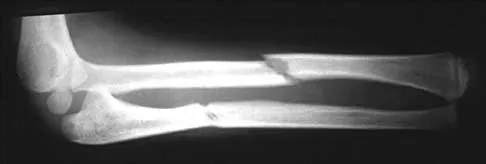

Question 15

Figure 31 shows the radiograph of an 8-year-old boy who has a swollen forearm after falling out of a tree. Examination reveals that all three nerves are functionally intact, and there is no evidence of circulatory embarrassment. Management should consist of

Explanation